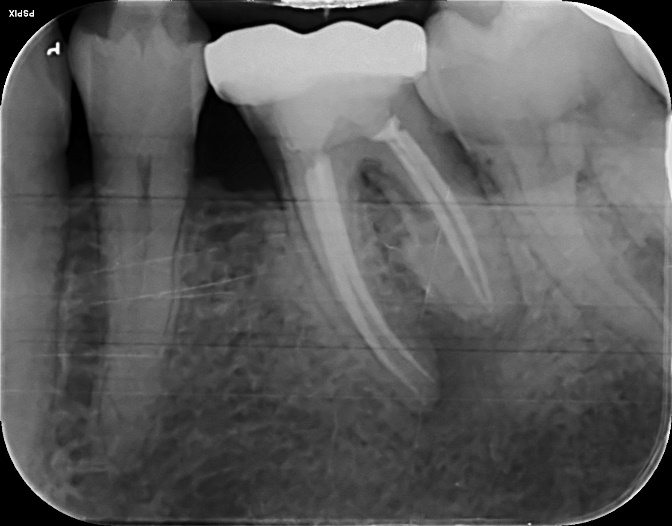

Lower Molar x2 curved roots Primary Root canal treatment and dental crown/rebuild

Lower Molar curved root Primary root canal treatment and rebuild

Lower Molar curved roots Re-root canal treatment with core rebuild